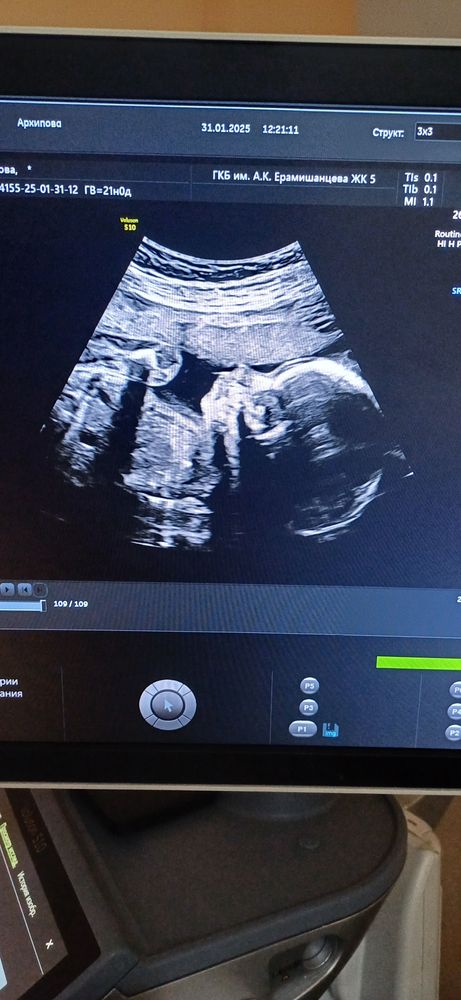

Пятничные замеры, 21 неделя и 2й скрининг

Что со вторым скринингом. У нас устроено так, что Г открывает направление, а записывает сама Жк, просто ставит перед фактом, что такого-то числа во столько-то у вас скрининг. Ок. 19 недель. Тишина. Я позвонила, меня заверили, что все ок, ждите, запишем:) 20 недель. Тишина. А ещё у меня было открыто направление на анализ мочи, пошла в жк за стаканчиками халявными и с оказией подошла на ресеп. Говорю, мол, а че со скринингом то, дамы? В четверг у меня 21 неделя. Они пошли узнавать и как давай бегать) Никто и не собирался меня никуда записывать😅 Они просто убрали куда-то мою карту и на этом всё. Перепугались, бегают, бегают. А все на неделю уже расписано. Мне смешно, но стою молчу. Я прошла скрининг платно. А если бы не прошла??? Вот бы 4.02 все так удивились, когда узнали бы, что все просрали. Нашли окно на сегодня:) Бонусом со страху записали на 25 февраля на гтт.

Съездила, посмотрела Агушу, все окей. За 2 недели набрала 200г примерно. Сейчас предполагаемый вес 400г. Доктор спросила знаю ли пол, хочу ли знать) подтвердили Агату:) Котик ну вылитая сестра:)) Муж говорит а если они одинаковые будут 😅 Ну, значит будут:))